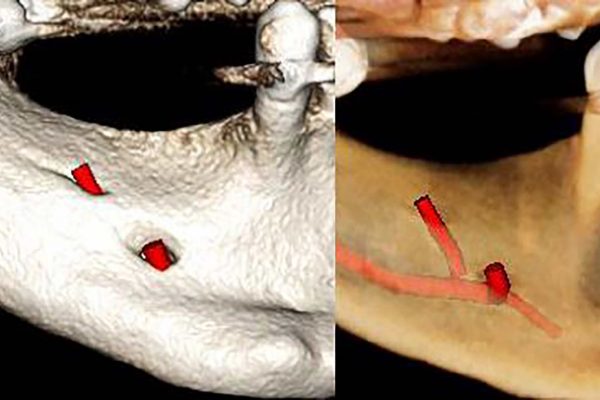

Implant planning at multiple sites in the mandible

This patient was sent to CT Dent for implant planning in multiple sites in the lower jaw. CT Dent provides…

Case of the month – planning for dental implants

CT Dent’s latest case of the month on planning for dental implants includes; the main findings, findings from the radiographic…

Implant dentistry

Case of the month – pre-implant assessment

Basic report for pathology only CBCT scanner: Kavo OP 3D Vision V17 CBCT imaging protocol: 16cm diameter x 10cm height Effective dose: 0.1…

Dentistry